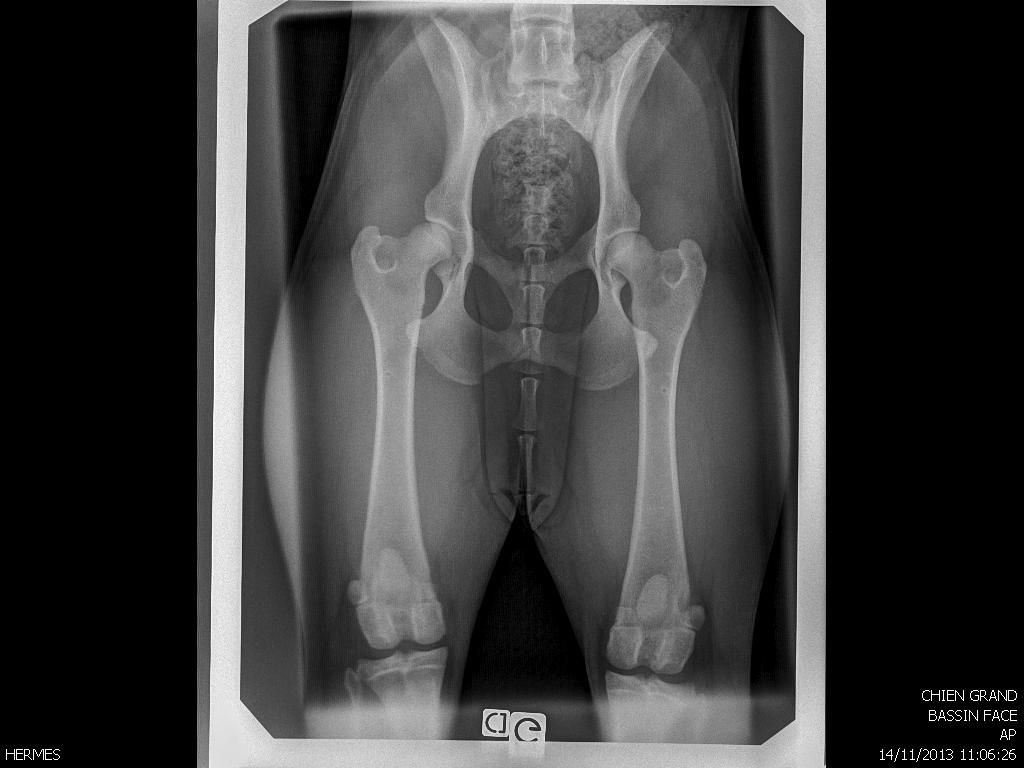

Déconnecté | Endormi pour radios |

Déconnecté | Bon debut de spondyose en L7 et S1 j'y allais pour une boiterie avant gauche et il a vu sa facon de marcher et il m'a dit qu'elle avait aussi un probleme derriere. sa n'a pas loupé. traitement d'1mois et anti inflammatoire 8 jours. pour la patte avant elle avait un blocage au coude et epaule mais pour la boiterie il dit qu'il peut y avoir une tendinite ou dechirure (dur a diagnostiquer chez le chien). 1 mois de repos pour remettre tout sa et apres selon evolution on verra. Mais je pense que je vais arreter. Je ne veux pas prendre de risque. il me l'a fortement conseiller si je voulais pas qu'elle risque d'etre HS dans 2 ans. meme si pas de probleme aux cervicales (lieu ou il y a le plus de choc en ring avec le mordant), sa raisonne jusqu'a la queue. voila. Affaire a suivre ![]() |